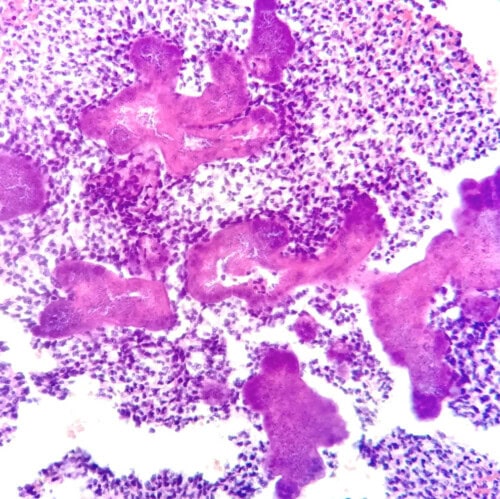

Les biopsies cutanées (LAPVSO) montrent un tissu de granulation dans lequel aucune structure épithéliale n’est visible. Ce tissu est infiltré de nombreux granulocytes neutrophiles plus ou moins altérés associés à une population inconstante de lymphocytes, plasmocytes et histiocytes. Au sein de cette lésion on observe plusieurs colonies bactériennes géantes constituée de coques et entourées d’un matériel éosinophile hyalin (phénomène de Splendore-Hoëppli).

Photos 6 et 7 : Examen histopathologique montrant principalement des granulocytes neutrophiles entourant des colonies bactériennes enveloppées dans un matériel éosinophile hyalin (JC Husson, LAPVSO, HE)